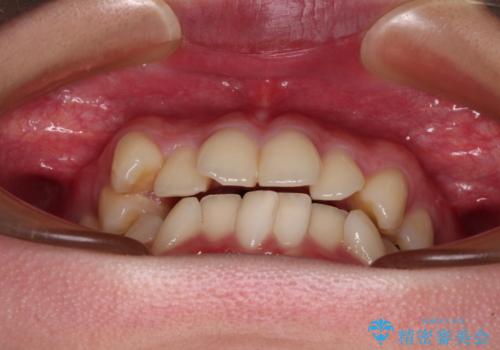

- 八重歯やクロスバイトを気にして来院された患者様です。

口元の突出感はありませんでしたが、デコボコが強く、非抜歯矯正とすると出っ歯仕上がりとなる可能性があったため、上下左右の第一小臼歯4本を抜歯し、ワイヤー装置にて矯正治療を行うこととしました。